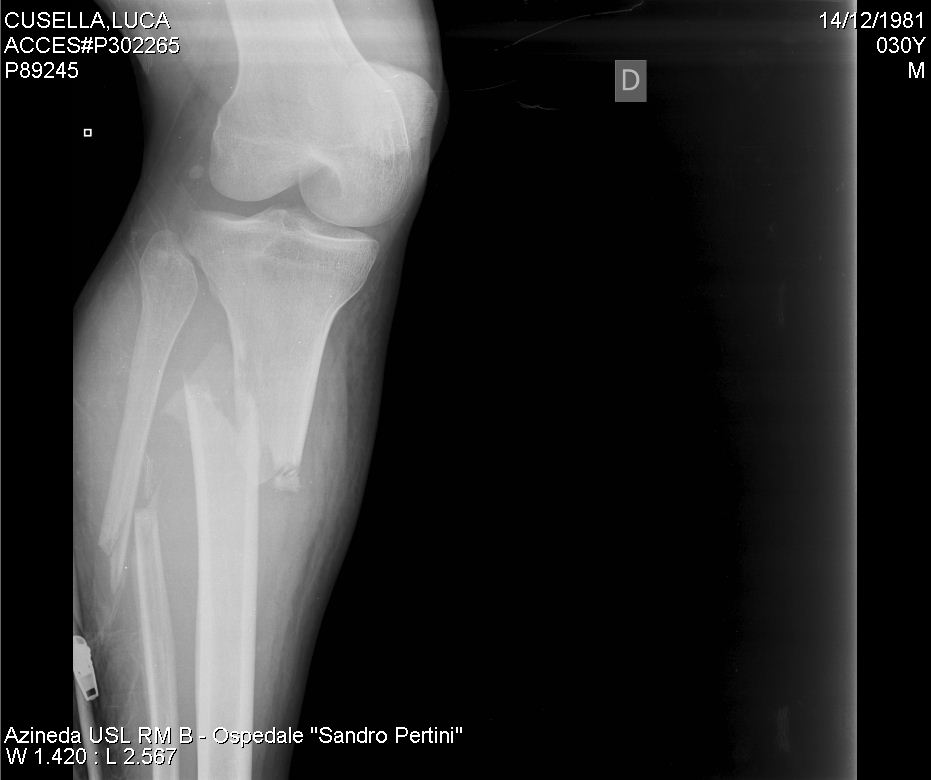

La tibia e il perone (o fibula) sono le due ossa che compongono il segmento distale dell'arto inferiore, cioè dal ginocchio in giù fino al piede.

Un video con immagini della mia gamba sx dopo l'incidente in moto. La frattura di tibia e perone, che nei casi più gravi diventa una frattura scomposta tibia e perone, è conseguente a forti traumi come per esempio accade cadendo con la moto, negli incidenti stradali e negli sport da contatto. Fortunatamente l'uomo, un sessantenne del paese, rimasto schiacciato dall'albero, ha riportato solo una frattura alla gamba sinistra: 7° giorno frattura tibia perone 6° dopo operazione con perno/chiodo endomidollare tibia. Buonasera, lo scorso novembre ho riportato una frattura scomposta del iii distale di tibia e perone trattata con chiodo endomidollare e successivamente ho rimosso la vite statica in zona ginocchio. Esperto in assicurazioni , gestione sinistri e risarcimento danni. Volevamo sapere i tempi di guarigione , se deve fare le fisioterapie e se dopo la guarigione ritorni a camminare come una volta. Il giovane australiano ha riportato la fratture della tibia e del perone della gamba destra, ed è stato sottoposto a un intervento chirurgico per stabilizzare le due fratture con placche e viti di compressione. Il pesante tronco gli ha spezzato sia tibia che perone. Il dolore è fortissimo il dott mi ha dato targin 5 mg 2 volte al dì, alla prima pastiglia mi è venuta un emicrania fortissima, posso alternare con tachipirina 1000 così passa mal di testa e attenuo dolore gamba? Erano all'incirca le 10 di mercoledì, 26 marzo. 4 видео 330 просмотров обновлен 22 дек. Ciao , mia nonna ha subito una frattura scomposta alla tibia ed al perone. Nel maggio 2004 ho avuta la frattura scomposta di tibia e perone durante una partita di calcio. Il problema e' quello, pur facendo agonismo ho avuto due gravi infortuni propio fuori dalle gare, l'anno scorso a giugno sono stato investito in pieno da un auto in allenamento in una strada semi deserta e questa volta sono caduto da fermo su un tombino spezzandomi di netto tibia e perone. Pagina creata per la squadra di calcio a 5 iscritta al campionato csi di carpi. Come praticamente tutte le altre ossa del corpo umano, anche tibia e perone possono essere oggetto di frattura a seguito di traumi rilevanti a loro carico.